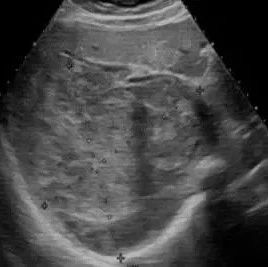

脾脏硬化性血管瘤样结节性转化超声表现1例

患者女,27岁,因体检发现脾门区肿瘤入院。超声检查:脾脏切面形态失常,实质点状强回声分布不均匀,脾门区可见一个大小为5.2 cm×4.3 cm×4.7